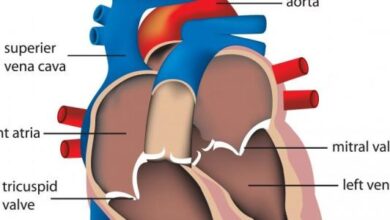

روماتيزم القلب أو داء القلب الروماتزميّ (بالإنجليزية: Rheumatic heart disease) هو حالة صحية تتمثل بتلف واحد أو أكثر من صمامات القلب بشكل دائم بسبب الإصابة بحُمّى الروماتيزم (بالإنجليزية: Rheumatic fever)؛ حيث تحدث المشكلة بعد الإصابة بعدوى البكتيريا العُقدية في حال عدم علاجها أو عدم علاجها بكشل كافٍ، فيستجيب الجهاز المناعي بتحفيز التهاب مستمر يُلحق الضرر بصمامات القلب.[١][٢]

كما بيّنّا سابقًا فإنّ روماتيزم القلب يحدث نتيجة المعاناة من حُمّى الروماتيزم، وبالرغم من أنّ الضرر الملحوظ في حالات روماتيزم القلب يتركز في الغالب في صمامات القلب، إلا أنّ أجزاء أخرى من القلب قد تتأثر كذلك، بما في ذلك بطانة القلب أو عضلته، وإنّ حدوث التهاب في هذه الأجزاء يُسبب التهاب القلب، ونتيجة هذا الضرر الحاصل في القلب قد يتشكّل نسيج ندبيّ على صمّامات القلب، ولا يزول بعد الشفاء من حمّى الروماتيزم، وقد يؤدي ذلك إلى اضطراب حركة الدم بين الصمامات، مثل تسّرب الدم بين الحجرات، أو عودة الدم بالاتجاه المعاكس، أو إعاقة حركة الدم بسبب تضيّق الصمّام واضطراب قدرته على الفتح والإغلاق بشكلٍ طبيعيّ، وقد يحتاج الشخص المصاب الخضوع لعمل جراحيّ لتصحيح الضرر الحاصل على صمّامات القلب في الحالات الشديدة.[٢][٣]